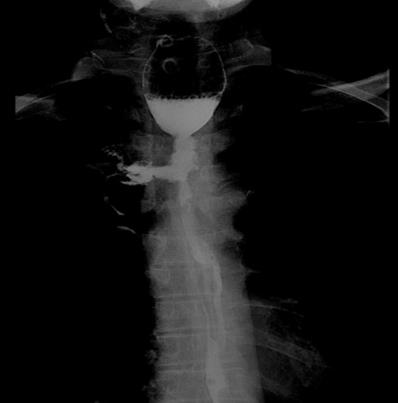

EF was a connection between the esophagus and adjacent organs [17]. The diagnosis of EF was routinely confirmed by cervical and chest CT, barium esophagography or endoscopy of the esophagus during RT or after RT. The common clinical manifestations of EF include dramatic cough with massive sputum or hematemesis, chest pain and fever. Types of EF include EMF (Esophageal-mediastinum fistula), ERF (Esophagorespiratory fistula) and AEF (Arterio-esophageal fistula). Typical imaging of EF seen in Fig 1-2.

Barium esophagography shows esophageal-mediastinum fistula.